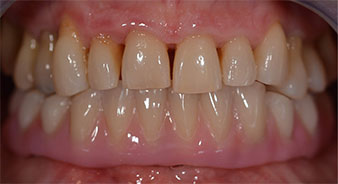

The impression and bite registration were then performed so that the dental technician could begin producing the provisional restoration immediately. This was then screwed in on the same day (Fig. 17 and 18).

Following the time required for the osseointegration, the final impression of the implants could be performed and the final denture produced accordingly (Fig. 19 and 20). At this point, the dentist and patient were able to decide together whether to use a ceramic or acrylic veneer and a zirconium or metal framework. In this case, Dr. Pascu’s team decided on an acrylic veneer based on the unclear prognosis for the maxillary dentition and the fact that tooth 24 is elongated. This type of veneer is generally considerably easier to adapt and can thus be subsequently altered to reflect the new situation in the maxilla.